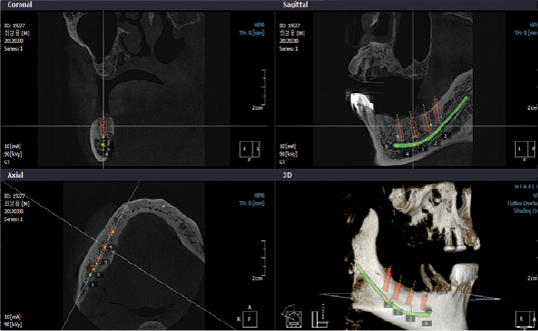

- Pianificazione terapeutica mediante trattamenti implantari

- Programmazione di chirurgia implatare guidata

- Follow up di trattamenti implantari